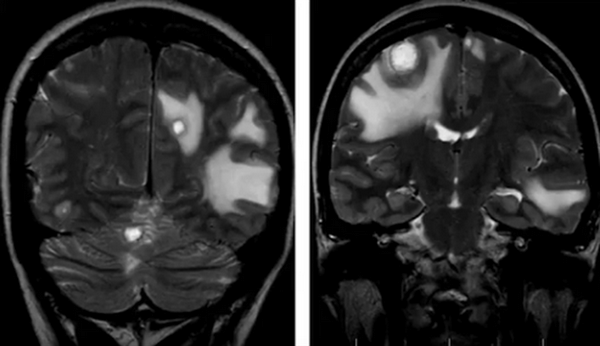

Нативная и контрастная МРТ: после усиления видны множественные мелкие метастазы головного мозга

Распознать опухоль головного мозга с помощью МРТ без контраста можно на продвинутой стадии. Малые новообразования скульптурируются значительно хуже или не видны совсем, что снижает ценность исследования. При высокой напряженности поля можно сделать нативную МРТ, снимки будут хорошего качества. Магнитно-резонансная томография выдает изображения в зависимости от запрограммированного типа сканирования, контрастирование упрощает выявление опухолей на любой стадии развития, проведение дифференциального диагноза между доброкачественным и злокачественным процессом. Побочные эффекты на введение препарата на основе хелатов гадолиния развиваются крайне редко, меньше чем у 1% людей. При наличии показаний отказываться от контрастного усиления не стоит. Пациентам, страдающим почечной или печеночной недостаточностью в декомпенсированной стадии, может быть выполнена обычная МРТ. Магнитно-резонансное сканирование без динамического контрастирования на томографе с небольшой мощностью обнаружит объемное поражение головного мозга значительных размеров. После внутривенного введения парамагнетика можно более точно определить локализацию, объем, степень инвазии, рассмотреть кровоснабжение опухоли, оценить индивидуальные особенности, что имеет значение для планирования лечения.